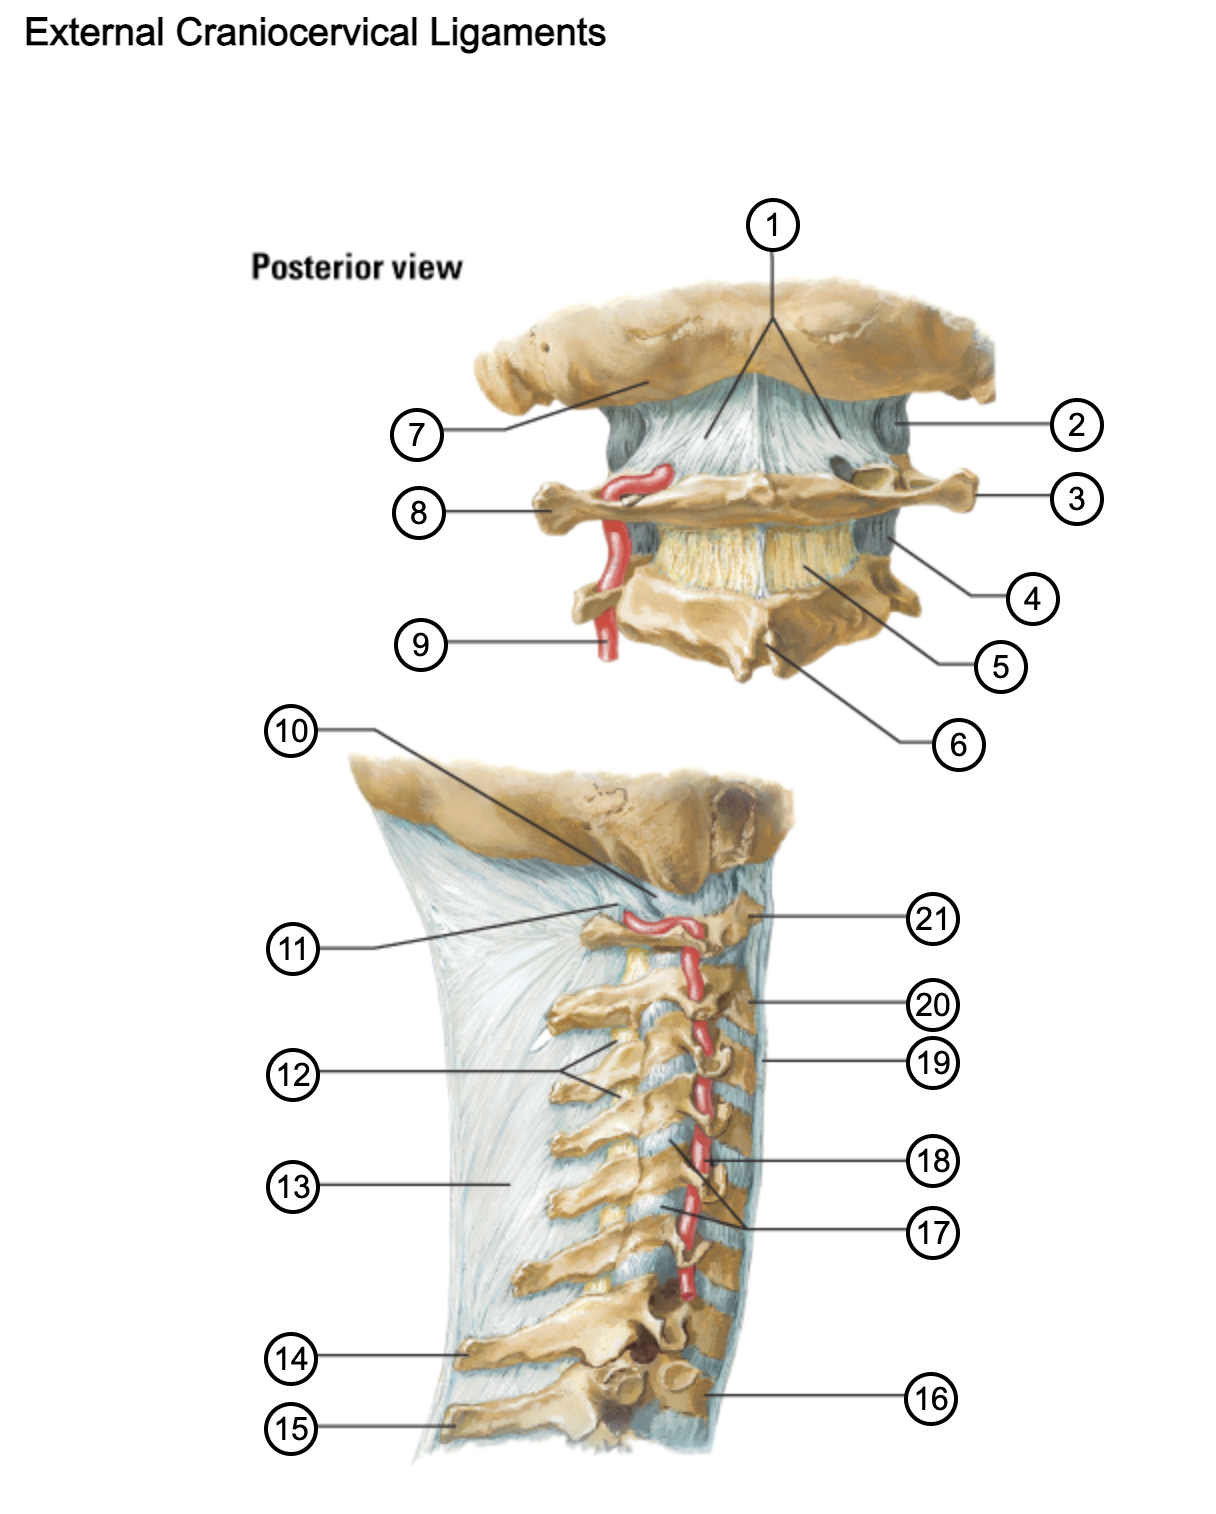

1

posterior antlantooccipital membrane

2

capsule of atlantooccipital joint

3

transverse process of atlas (C1)

4

capsule of lateral atlantoaxial joint

5

ligamenta flava

6

spinous process

7

occipital bone

8

transverse process of atlas (C1)

9

vertebral artery

10

capsule of atlantooccipital membrane

11

posterior atlantooccipital membrane

12

ligamenta flava

13

nuchal ligament

14

spinous process of C7 vertebra

15

spinous process of T1 vertebra

16

T1 vertebra

17

zygapophysical joints (C4-5 and C5-6)

18

vertebral artery

19

anterior longitudinal ligament

20

body of axis

21

Atlas (C1)